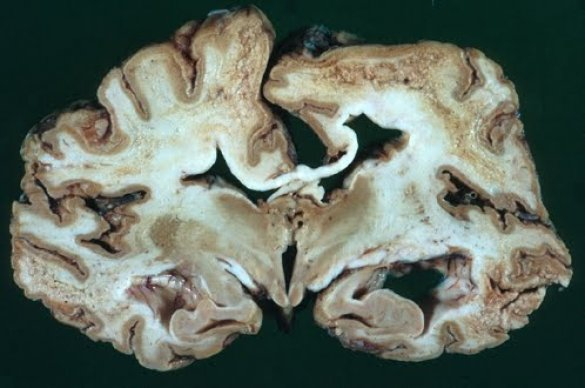

1. Болезнь Крейтцфельтда

Якоба 1 место среди смертельных инфекций досталось губчатой энцефалопатии, она же болезнь Крейтцфельда-Якоба. Инфекционный агент-возбудитель обнаружен сравнительно недавно – с прионными заболеваниями человечество познакомилось в середине ХХ века. Прионы – белки, вызывающие нарушение функций, а затем и гибель клеток. Из-за особой устойчивости могут передаваться от животного к человеку через пищеварительный тракт – человек заболевает, съев кусок говядины с нервной тканью зараженной коровы. Болезнь дремлет годами. Затем у пациента начинают нарастать расстройства личности – он становится неаккуратным, сварливым, впадает в депрессию, страдает память, иногда – зрение, вплоть до слепоты. За 8-24 месяца развивается деменция (слабоумие), больной погибает от нарушений мозговой деятельности. Заболевание очень редкое (за последние 15 лет заболело всего 100 человек), но абсолютно неизлечимое.